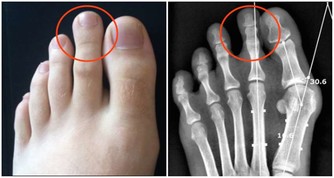

頸椎病現在的基本概念,是以頸椎椎間盤退變為主要病變基礎,包括頸周圍肌肉、關節繼發性改變和相鄰椎體退變增生直到壓迫神經血管等,並誘發與之相關臨床病症和體徵。

長期頸部前伸、頭部前屈,頸後部肌肉、韌帶就會處於被牽張的狀態,超過30分鐘時就會有疲勞感。超過2小時,就會造成肌肉、韌帶拉傷。長期下來,頸椎生理曲度變小、消失或反張,對椎間盤的支撐和保護作用下降,這時就容易出現頸椎病啦。